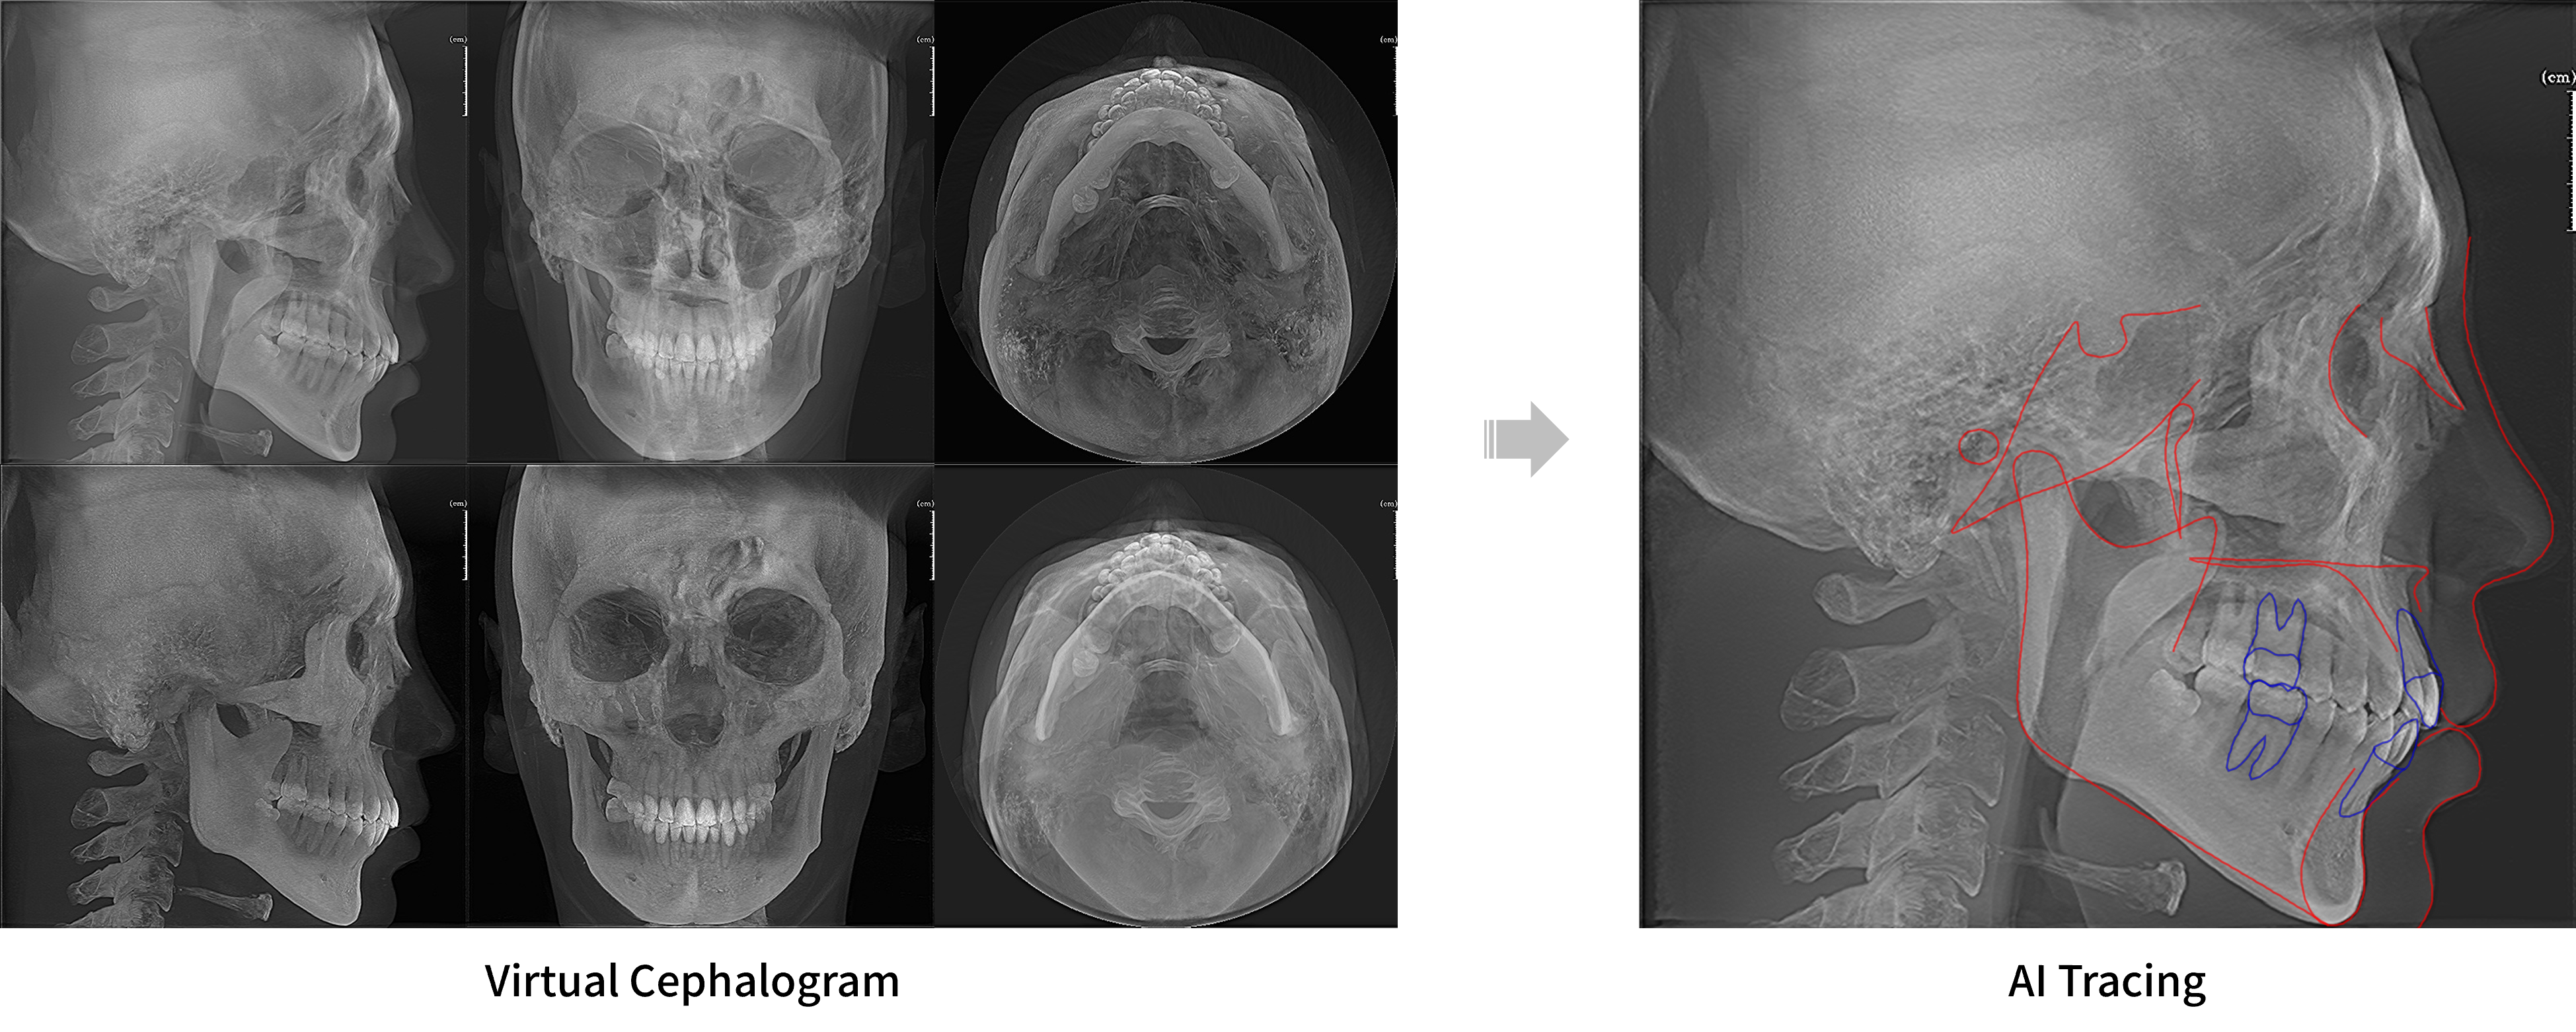

Virtual Cephalogram & AI Tracing

Generate cephalometric images from CT data without a cephalometric unit, with AI automatically recognizing orthodontic landmarks to save time and enhance diagnostic accuracy.